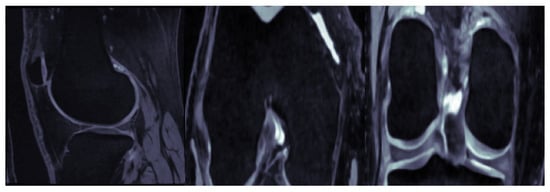

3. Materials

3.1. Image Dataset

3.2. Image Preprocessing